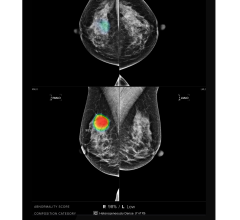

Nov. 6, 2025 — Lunit, a provider of AI for cancer diagnostics and precision oncology, recently announced that Volpara ...